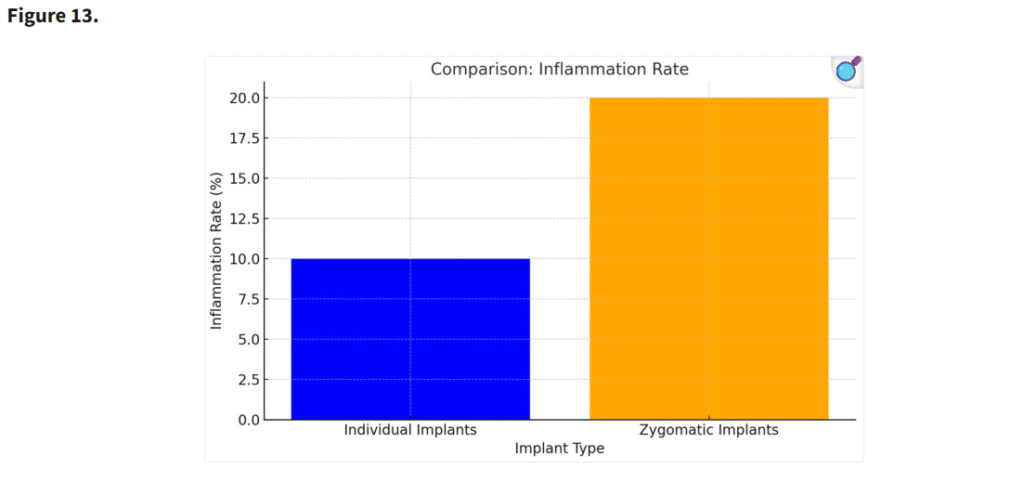

3.5. 術後粘膜の厚さ

術後の粘膜厚は、個別設計インプラントを使用した患者でより安定していた。個別インプラントに伴う周囲構造への機械的ストレスの軽減が、術後成績の改善に寄与したと考えられる(p < 0.05)(Figure 13)。

エクストラマキシラリー法によるインプラント埋入に関連した副鼻腔炎は、臨床的にザイゴマインプラント周囲で観察される炎症およびCBCT画像上の炎症の原因である(p < 0.05)